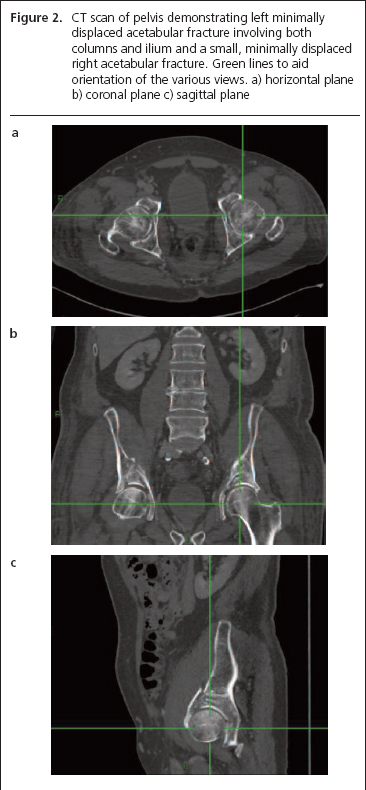

Due to the significant hip and lateral thigh pain, a pelvic x-ray was performed which demonstrated no obvious abnormalities (Figure 1). However, due to the clinical suspicion of acetabular fractures due to reduced range of motion of both hips on clinical examination, further imaging was sought. CT pelvis revealed a left minimally displaced acetabular fracture involving both columns and ilium and a small, minimally displaced right acetabular fracture (Figure 2). Other possible differentials included myopathy and malignant causes of fracture but were excluded by normal creatine kinase, lactate and calcium levels.

Figure 2